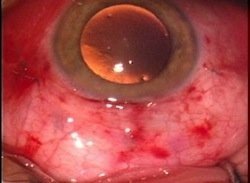

Figura 2. Vitrectomía transconjuntival a través de trocares 23G, cirugía que se realiza sin suturas.